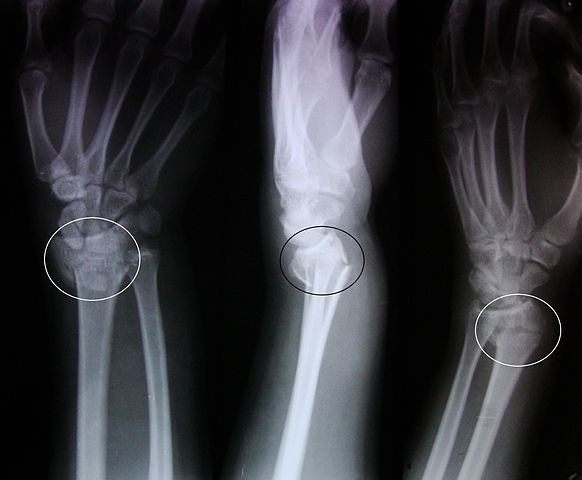

The fracture is diagnosed by certain imaging studies – computed tomography and radiography.

Fracture: The fracture is diagnosed by computed tomography and radiography.

- The fracture is diagnosed by computed tomography and radiography, while the sprain is easily diagnosed based at the patient’s complaints and how the trauma has occurred. Imaging studies are used if the injury is more severe.

[3]Image credit: https://upload.wikimedia.org/wikipedia/commons/thumb/d/dc/Colles_fracture.JPG/582px-Colles_fracture.JPG